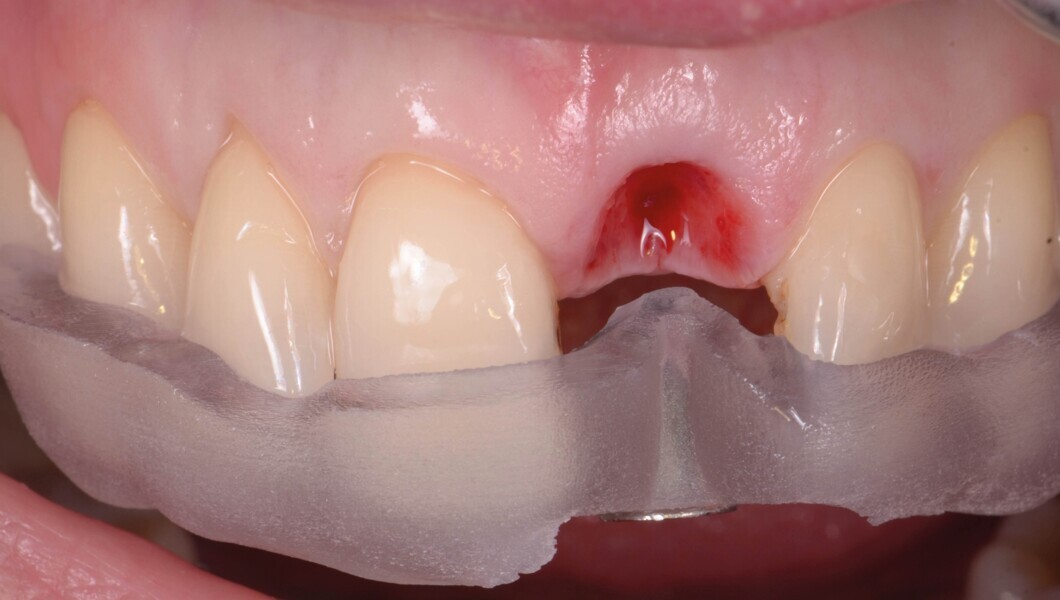

Une fistule avec écoulement purulent est présente en regard de l’apex de la dent. Une tomodensitométrie volumique a faisceau conique (CBCT) est réalisée pour évaluer l’environnement péri-dentaire : l’épaisseur de l’os vestibulaire, la forme de l’alvéole et la position de la racine sur le plan sagittal (Figs. 2–3). Une fracture radiculaire est mise en évidence.

Fig. 4 : Extraction atraumatique de la dent 21.

Fig. 5a : Après l’extraction

Fig. 5b : Après l’extraction